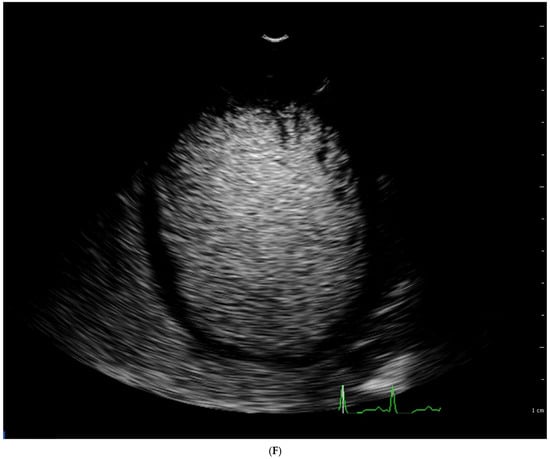

4.1. Echocardiography

| Chin [3] | ECHO | The ratio of the distance from the deepest trabecular recess to the epicardial surface (X) and the distance from the tip of the trabeculation to the epicardial surface (Y) | Long axis, end diastole | X/Y ≤ 0.5 |

| Stöllberger [47] | ECHO | Ratio of compacted and non-compacted endocardium. Presence of at least 3 trabeculations protruding in the left ventricle apically from papillary muscle, presence of the blood flow between trabeculations. | Four chamber, end diastole | NC/C > 2 |

| Jenni [33] | ECHO | Ratio of compacted and non-compacted endocardium. Absence of coexisting cardiac abnormalities, the presence of deep trabeculations, which are filled with blood | Short axis, end systole | NC/C ≥ 2 |